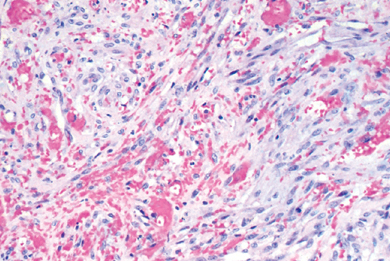

left main coronary artery 2 days after an MI. what histologic changes are present?

two days after MI: heart muscle will show myofiber necrosis, edema, and focal hemorrhage. this artery shows necrosis of cardiac myocytes and infiltrates of neutrophils

35 yom with MI, L main coronary artery two days later. what underlying disease does the patient have?

familial hypercholesterolemia